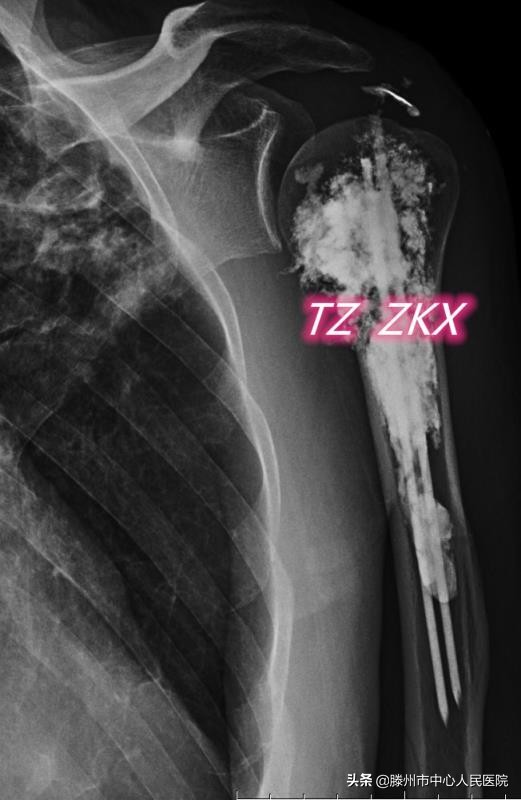

8月11日,张开贤主任医师团队在麻醉科的协助下,采用臂丛麻醉,在CT引导下经皮穿刺,首先对病变区域进行微波消融,利用高温使肿瘤发生凝固性坏死,然后在肱骨髓腔内置入两根克氏针,最后注射骨水泥,使克氏针、骨水泥与肱骨融合在一起,从而起到杀灭肿瘤、缓解疼痛、增加骨骼的稳定性、预防病理性骨折的作用。

微波消融联合钢筋混凝土技术治疗骨转移为国内领先的微创治疗技术,优势在于:在臂丛麻醉下进行,减少了全身麻醉对身体的不良影响;经皮穿刺完成整个治疗流程,创伤小,术后恢复快,住院时间短;在CT引导下进行,能精准地视察克氏针的空间位置、骨水泥的分布及渗漏情况,保证了治疗的安全性,同时与DSA下操作相比,减少了射线对医务人员的辐射。